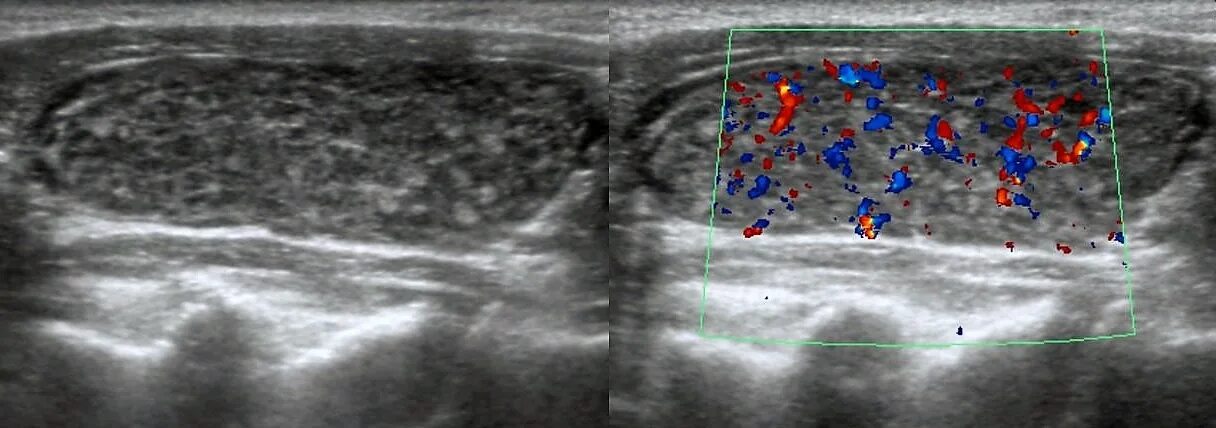

Выраженные диффузные